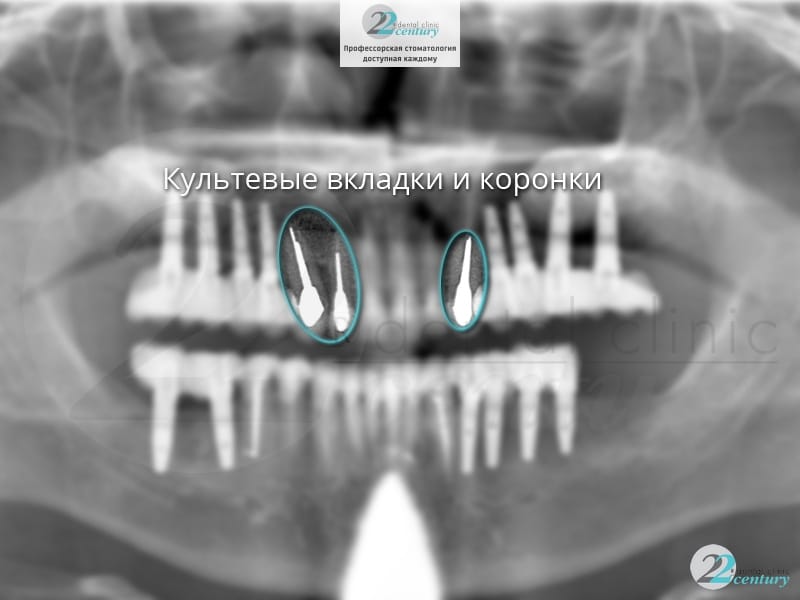

Фото выполненных работ в стоматологии «22 Век»